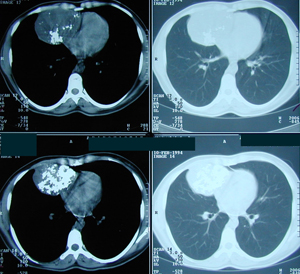

Περίπτωση Νο 3

Εικόνα 1

Αξονική τομογραφία θώρακος. Διακρίνεται ευμεγέθης όγκος του θωρακικού τοιχώματος με υπεζωκοτική συλλογή που προκαλεί ατελεκτασία του κάτω λοβού του δεξιού πνεύμονος.